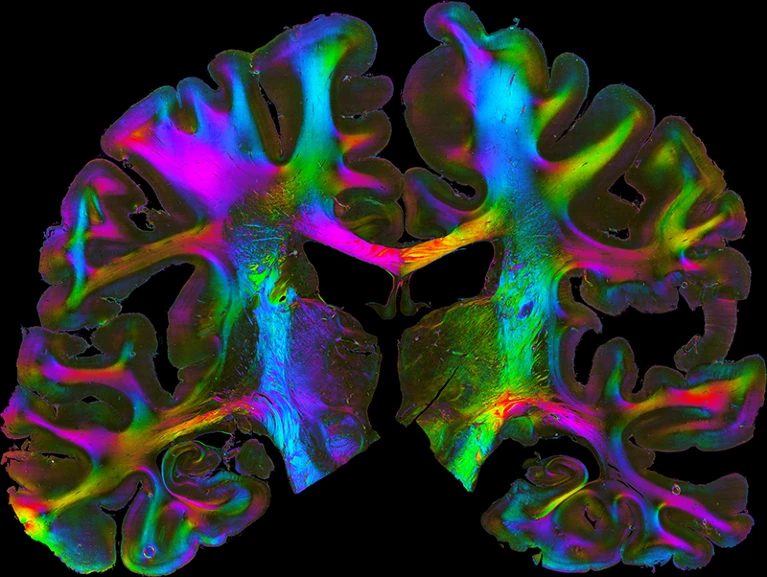

HBP详细描述了人类大脑的解剖结构

人脑切片,显示连接不同区域的纤维结构。资料来源:德国科学研究中心